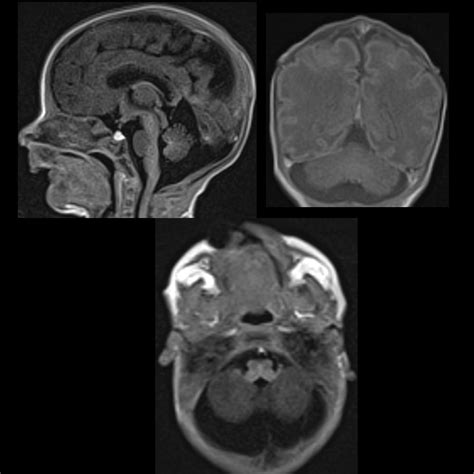

In the case of a Mega Cisterna Magna, this space is enlarged, which can be due to various reasons, including congenital anomalies, hydrocephalus, or other neurological conditions. The enlargement can be detected through imaging techniques such as magnetic resonance imaging (MRI) or computed tomography (CT) scans.

Diagnosing a Mega Cisterna Magna involves a combination of clinical evaluation and imaging studies. The most commonly used imaging techniques include:

• Magnetic Resonance Imaging (MRI): MRI provides detailed images of the brain and spinal cord, allowing for the visualization of the cisterna magna and any associated abnormalities. It is particularly useful in detecting congenital anomalies and neurological conditions.

• Computed Tomography (CT) Scans: CT scans use X-rays to create cross-sectional images of the brain. While not as detailed as MRI, CT scans can still provide valuable information about the size and shape of the cisterna magna.